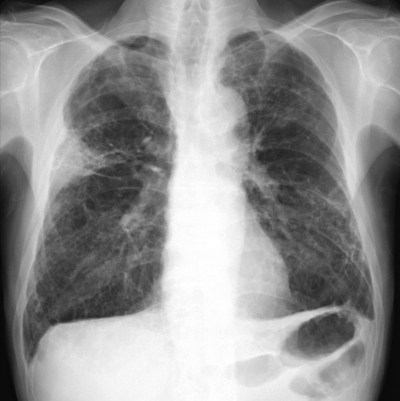

体温 36.6 ℃。脈拍 76/分、整。血圧 132/76 mmHg。呼吸数 12/分。SpO2 95 % (room air)。両側胸部で fine crackles を聴取する。呼吸機能検査:VC 3.5 L、FEV1 2.2L。心電図、心エコー検査で異常を認めない。胸部エックス線写真及び胸部単純CTを別に示す。